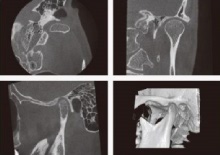

歯科用CT・パノラマ・デンタル撮影装置

被曝量の少ない3次元撮影が可能な歯科用CT・パノラマ撮影・デンタル撮影を導入しています。車椅子に乗ったままの撮影・検査も可能です。

CT撮影エリア

CT顎関節

パノラマ顎関節4分割

CT+パノラマ複合機で撮影)